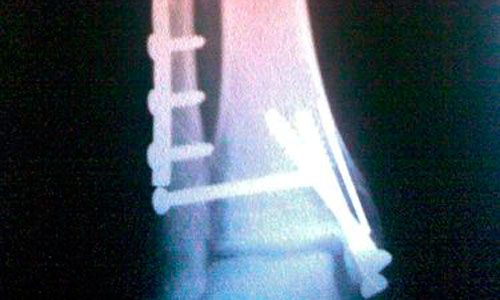

La preocupación por la sobrexposición a la radiación, debido al uso excesivo de la imaginología médica, ha pasado a primer plano en los últimos años. Ahora, un estudio dirigido por investigadores de la Universidad de California, en San Francisco (UCSF), y el Grupo del Instituto para la Investigación sobre la Salud, muestra que la imagen médica es cada vez más utilizada, incluso en las Organizaciones de Mantenimiento de Salud (Health Maintenance Organizations, HMOs).

El trabajo mostró un dramático incremento en las tasas de toma de imágenes, y una duplicación de la proporción de pacientes que sufrieron exposición a radiaciones altas, y muy altas, desde 1996 hasta 2010. El número de exámenes por ultrasonido se duplicó, el número de tomografías computarizadas (TC) se triplicó, y  se cuadruplicó el número de imágenes por resonancia magnética.

El aumento de la exposición a la radiación, debido a la imagen médica, es una causa de preocupación pública por el riesgo de cáncer que conlleva. Las técnicas de imagen que utilizan radiación ionizante (como las tomografías computarizadas) tienen el potencial de causar cáncer y, ??debido a la creciente utilización de estas técnicas en las últimas dos décadas, algunas estimaciones predicen que el 2 por ciento de todos los cánceres en el futuro serán el resultado de la exposición a las radiaciones.

Para sorpresa de los investigadores, para los pacientes en estos sistemas, al igual que para el resto de la población de los EE.UU., la cantidad media de radiación ha aumentado en las últimas dos décadas. El nuevo estudio mostró una duplicación de las tasas de formación de imágenes y, en 2010, por cada 100 pacientes adultos, se realizaron alrededor de 20 TC. Además, un número significativo de individuos en estos sistemas se someten a pruebas repetidas, por lo que están acumulando la dosis de radiación que se encuentra en el rango donde el cáncer es una preocupación real.